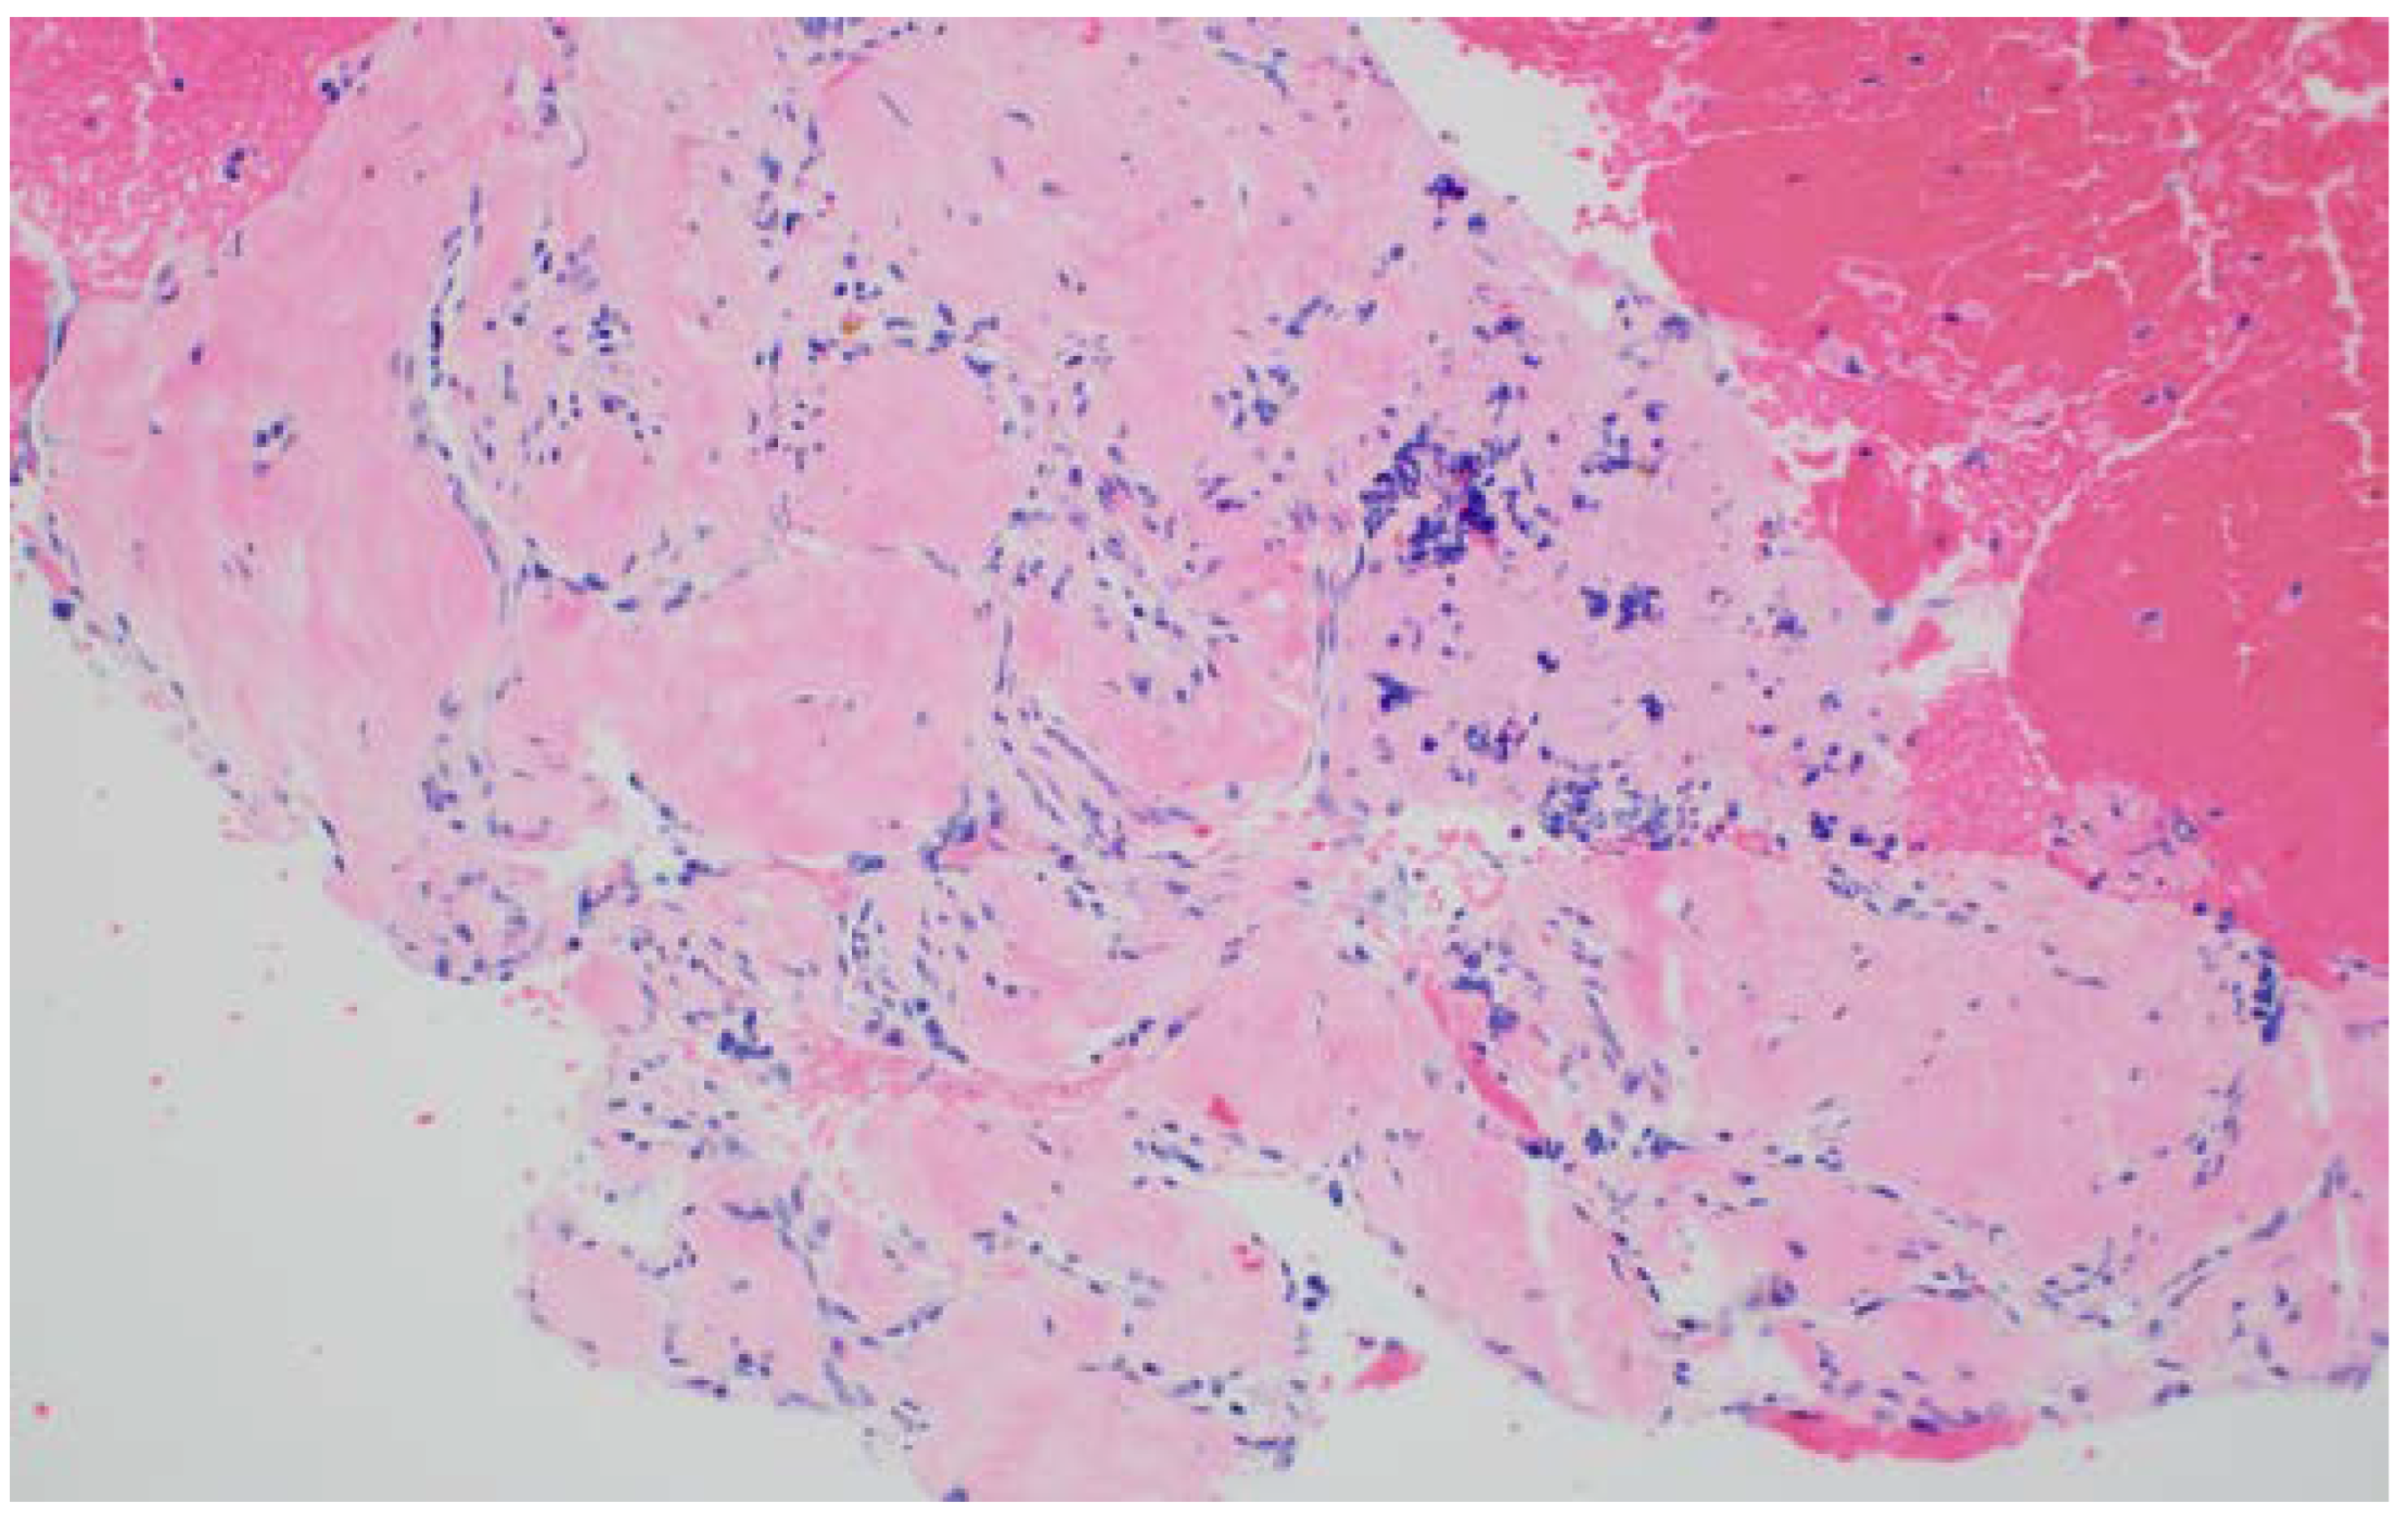

EUS-Guided Needle-Based Confocal Laser Endomicroscopy (EUS-nCLE)